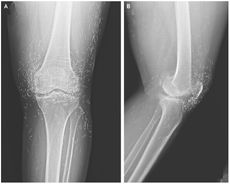

Diagnostic dilemma: After surgery, a 17-year-old could speak only a foreign language

By Christoph Schwaiger published

While waking up from knee surgery, a 17-year-old boy temporarily lost his ability to speak in his native language.